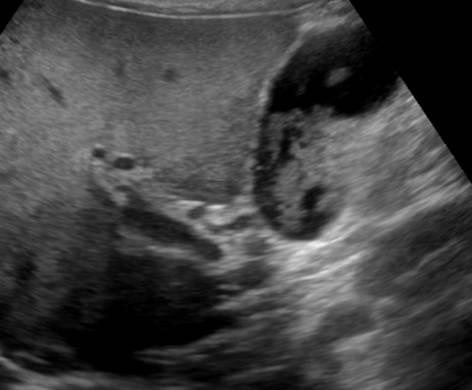

Bùn túi mật

Bùn túi mật - Ảnh 3

» Thông tin: Nam giới – 60 tuổi.

» Lâm sàng: Đau mạn sườn phải.